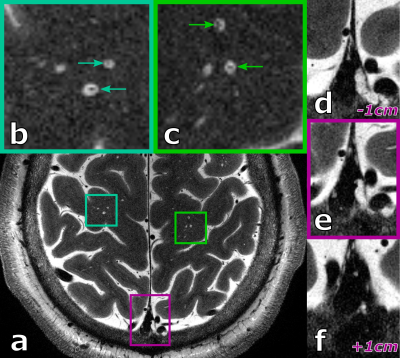

Figure 2: Ultra high resolution, axial slices of a healthy 38 years old male showing perivascular spaces (green boxes). Zoomed in versions in (b) and (c) show clearly vessels within some perivascular space (green arrows). Hyperintense structures in the sinus (magenta box) and slices positioned 1 cm above and below (d),(f) show hyperintense structures penetrating through the venous vessels.